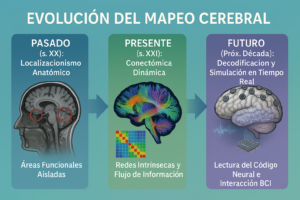

Introducción el Fin del Localizacionismo y el Nacimiento de la Conectómica. La neurociencia de mucho el siglo XX, funcionó con un modelo mayormente «localizacionista». Influenciados por los importantes descubrimientos de Broca y Wernicke, concebimos el cerebro como un conjunto de módulos separados, cada uno con una tarea concretas un lugar para el habla, otro para ver, y uno mas para la memoria de trabajo. Este enfoque aunque fundamental, representó una simplificación exagerada de la biología.

La ultima década presenció un cambio profundo, causado por grandes proyectos como el Human Connectome Project (HCP) y las neuroimágenes de super-alta resolución. Ahora, no es solo las «áreas», también estudiamos «redes».

Hoy dia, entendemos el cerebro no es solo islas funcionales, mas bien un sistema dinámico y complejo, tipo una orquesta sin un director central ¡vaya!, la cognición, emoción, consciencia surgen por la integración temporal de redes neuronales dispersas espacialmente.

Este articulo examina hallazgos más recientes sobre la funcionalidad cerebral; de este enfoque novel —la conectómica— y como esos mapas dinámicos transforman el diagnóstico neurológico, la planificación neuroquirúrgica, y también las intervenciones psiquiátricas.

El diseño de las Redes Funcionales Intrínsecas. Este mapa revela la posición de las tres «super-redes» cognitivas en la corteza. Arriba (Azul): Red por Defecto (DMN), funcionando en la cognición interna. Centro (Naranja): Red Ejecutiva Central (CEN), que está activa cuando hay tareas externas. Abajo (Verde): La Red de Relevancia (SN), que funge como un cambio dinámico entre la DMN y la CEN, hallando estímulos cruciales.

Hemos ingresado a una época nueva, ya! La cartografía cerebral actual, potenciada por la unión multimodal de la conectividad estructural (DTI) y la funcional dinámica (rs-fMRI, MEG), ¡ha destrozado esa visión modular del cerebro! Nos ha revelado un órgano definido por su integración a gran escala, gobernado por redes internas, como la DMN, CEN y SN, cuyo balance dinámico es la base de la experiencia humana.